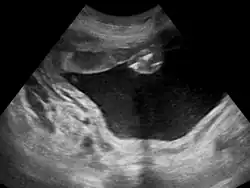

Poli-hidrâmnio (ou polidrâmnio) é uma condição médica na qual há excesso de líquido amniótico no saco amniótico. Essa alteração acontece em 1% das gravidezes, e é tipicamente diagnosticada quando o índice de líquido amniótico é superior a 24 cm.[1]